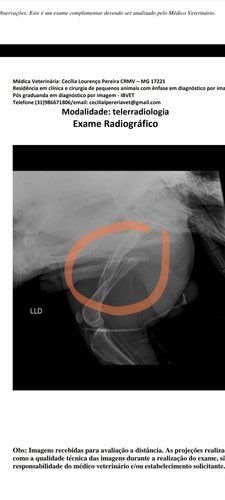

Fui atropelado no dia 17/07. Passei por duas cirurgias. Tive várias fraturas no fêmur e na região pélvica, estou anêmico e com alteração no fígado.